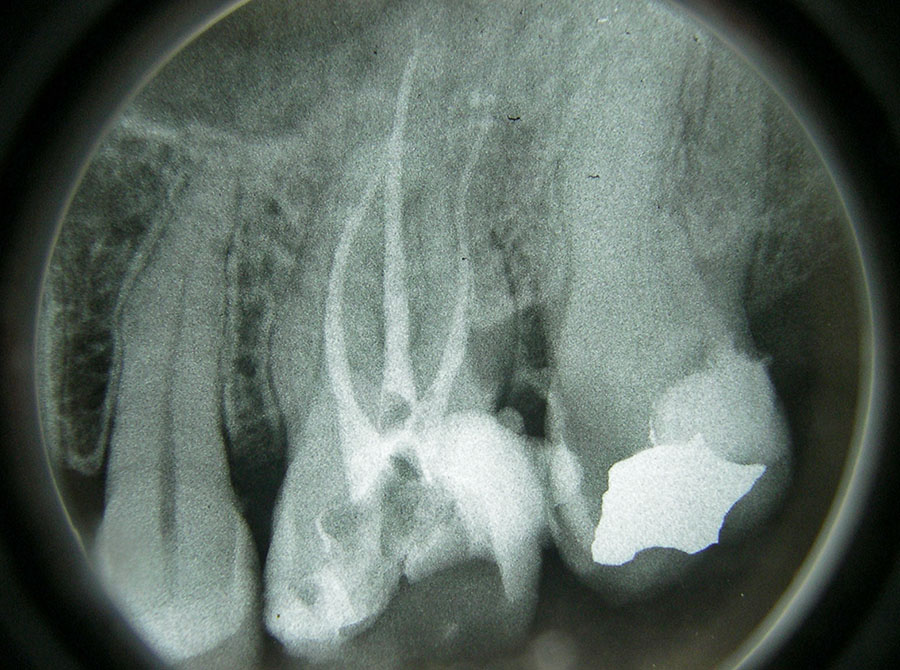

Entscheidend für den Langzeiterfolg einer Wurzelkanalbehandlung ist die exakte Füllung des gesamten Wurzelkanals bis zur Wurzelspitze. Daher verlassen wir uns hier nicht nur auf Röntgenbilder, sondern messen mit modernen Zusatzgeräten elektronisch die Länge jedes Wurzelkanals .Die Aufbereitung der Kanäle erfolgt teils von Hand, teils maschinell mit speziell dafür entwickelten, drehmomentbegrenzten Motoren und hochflexiblen Einmal-Feilen. Vor der endgültigen Wurzelfüllung wird bei uns jeder Wurzelkanal laser-sterilisiert, d.h. evtl. noch vorhandene Bakterien werden durch Zufuhr hochenergetischen Laserlichts über flexible Glasfasern abgetötet.